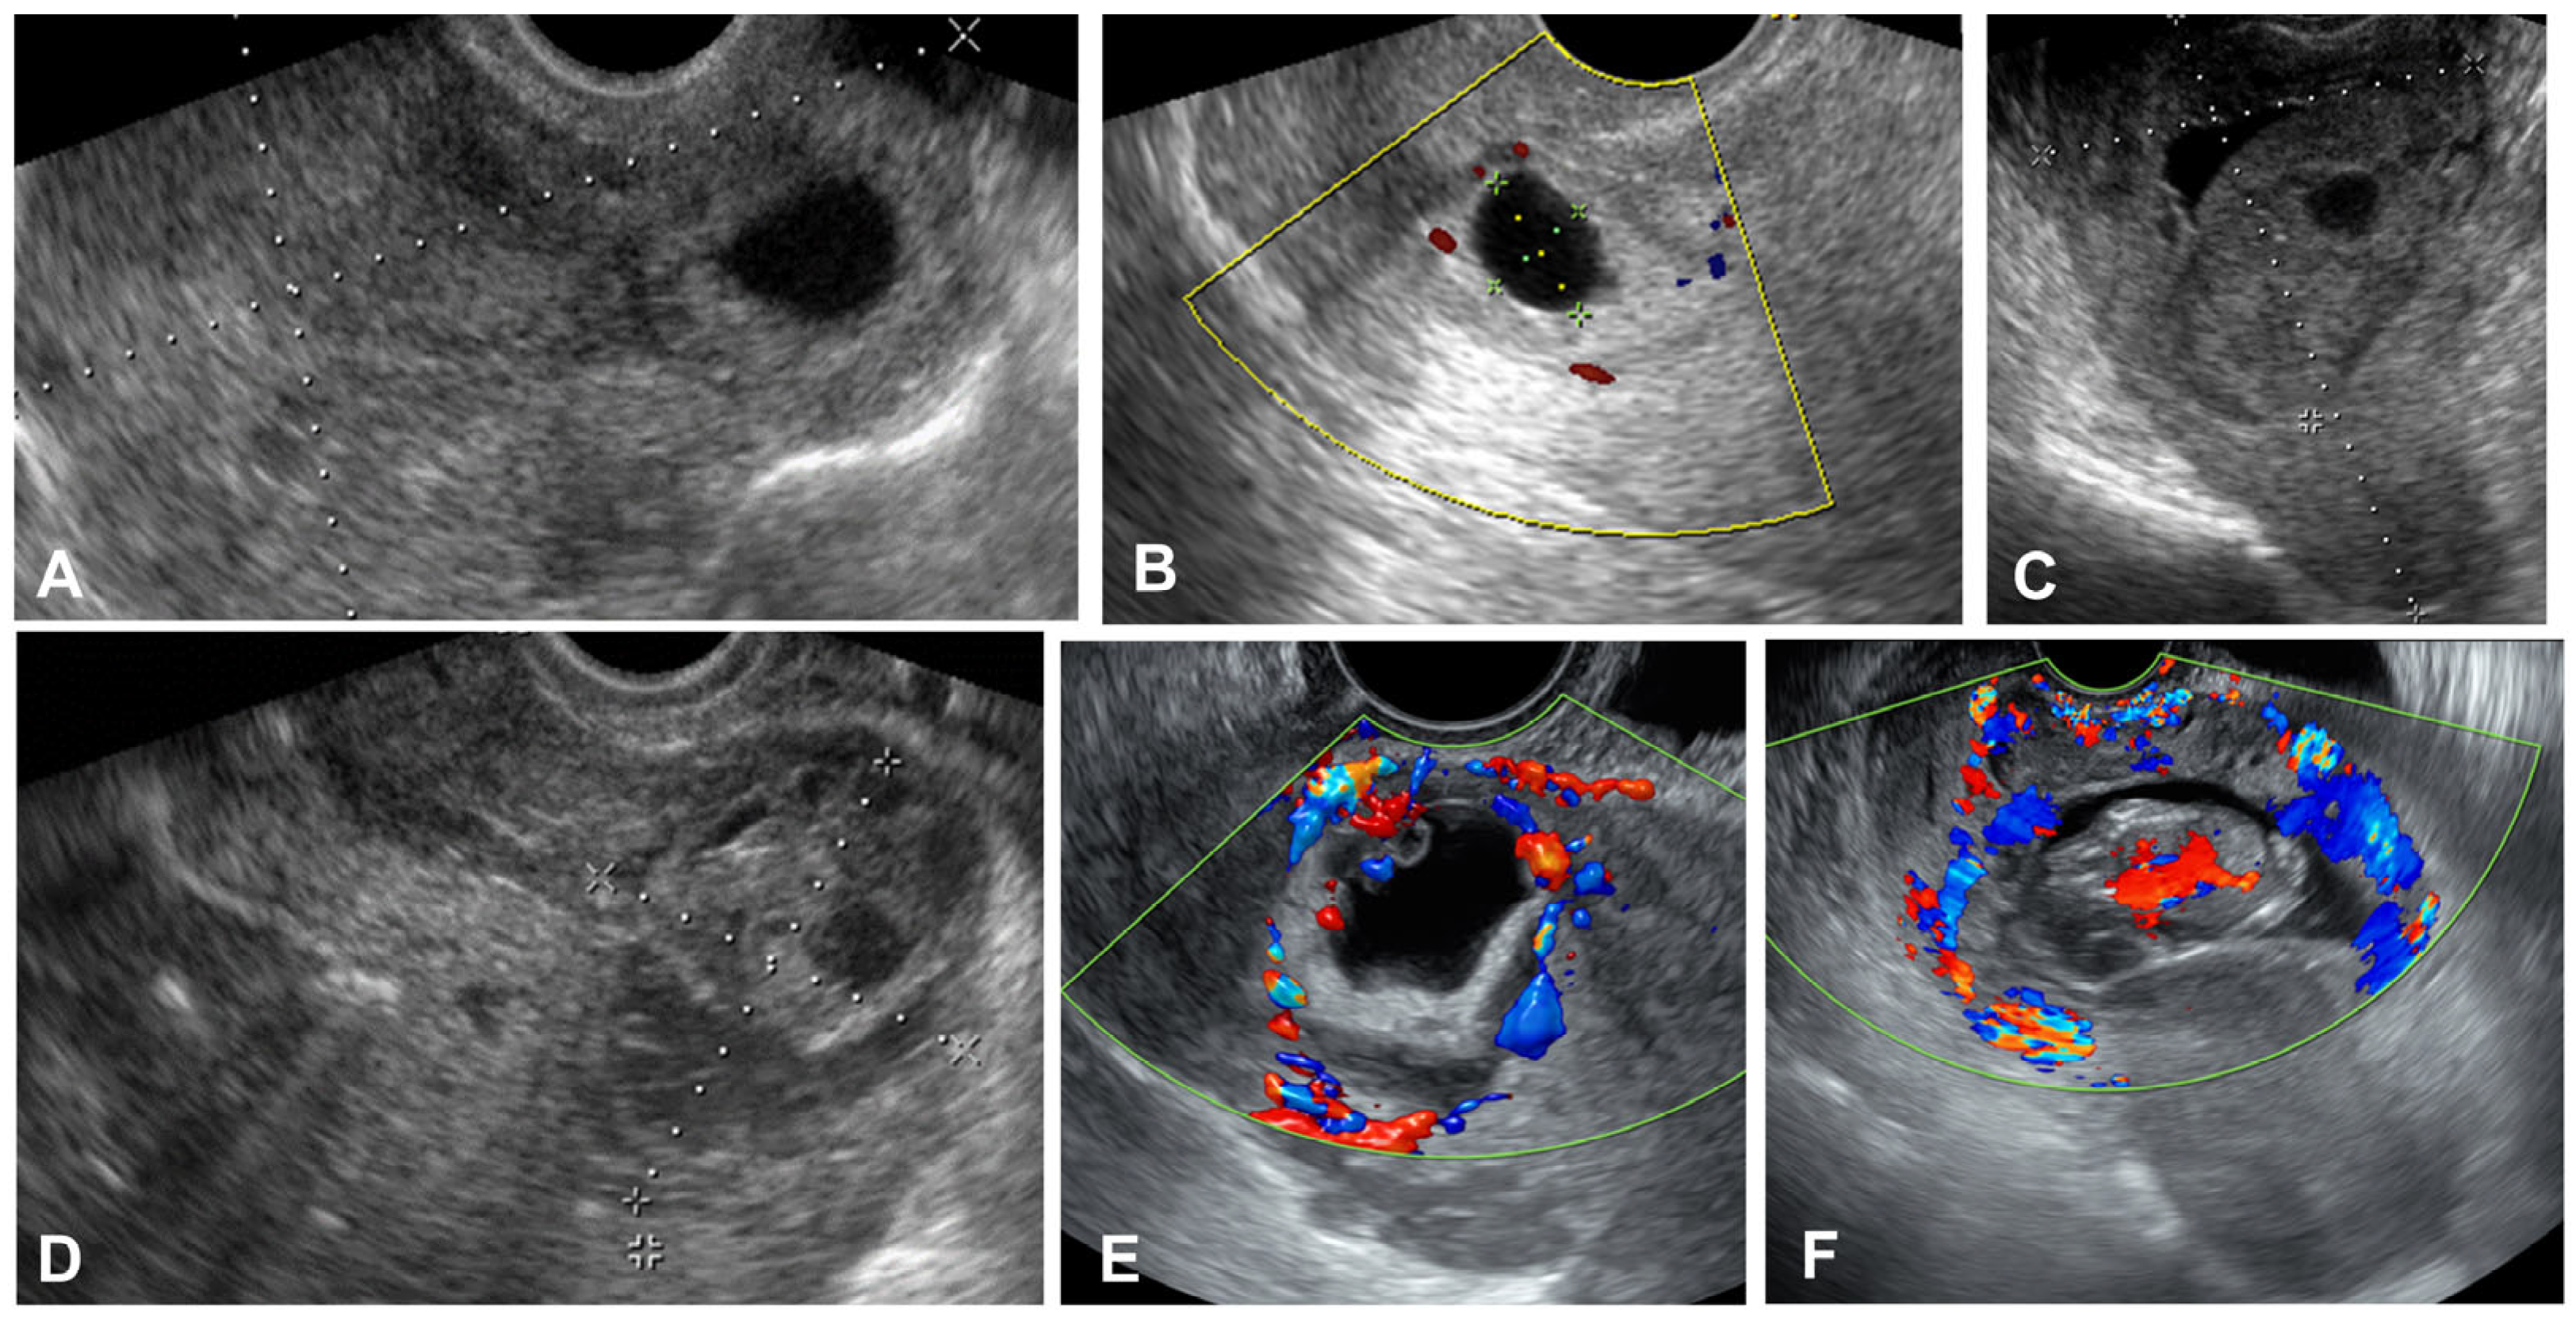

2.3. Imaging Acquisition